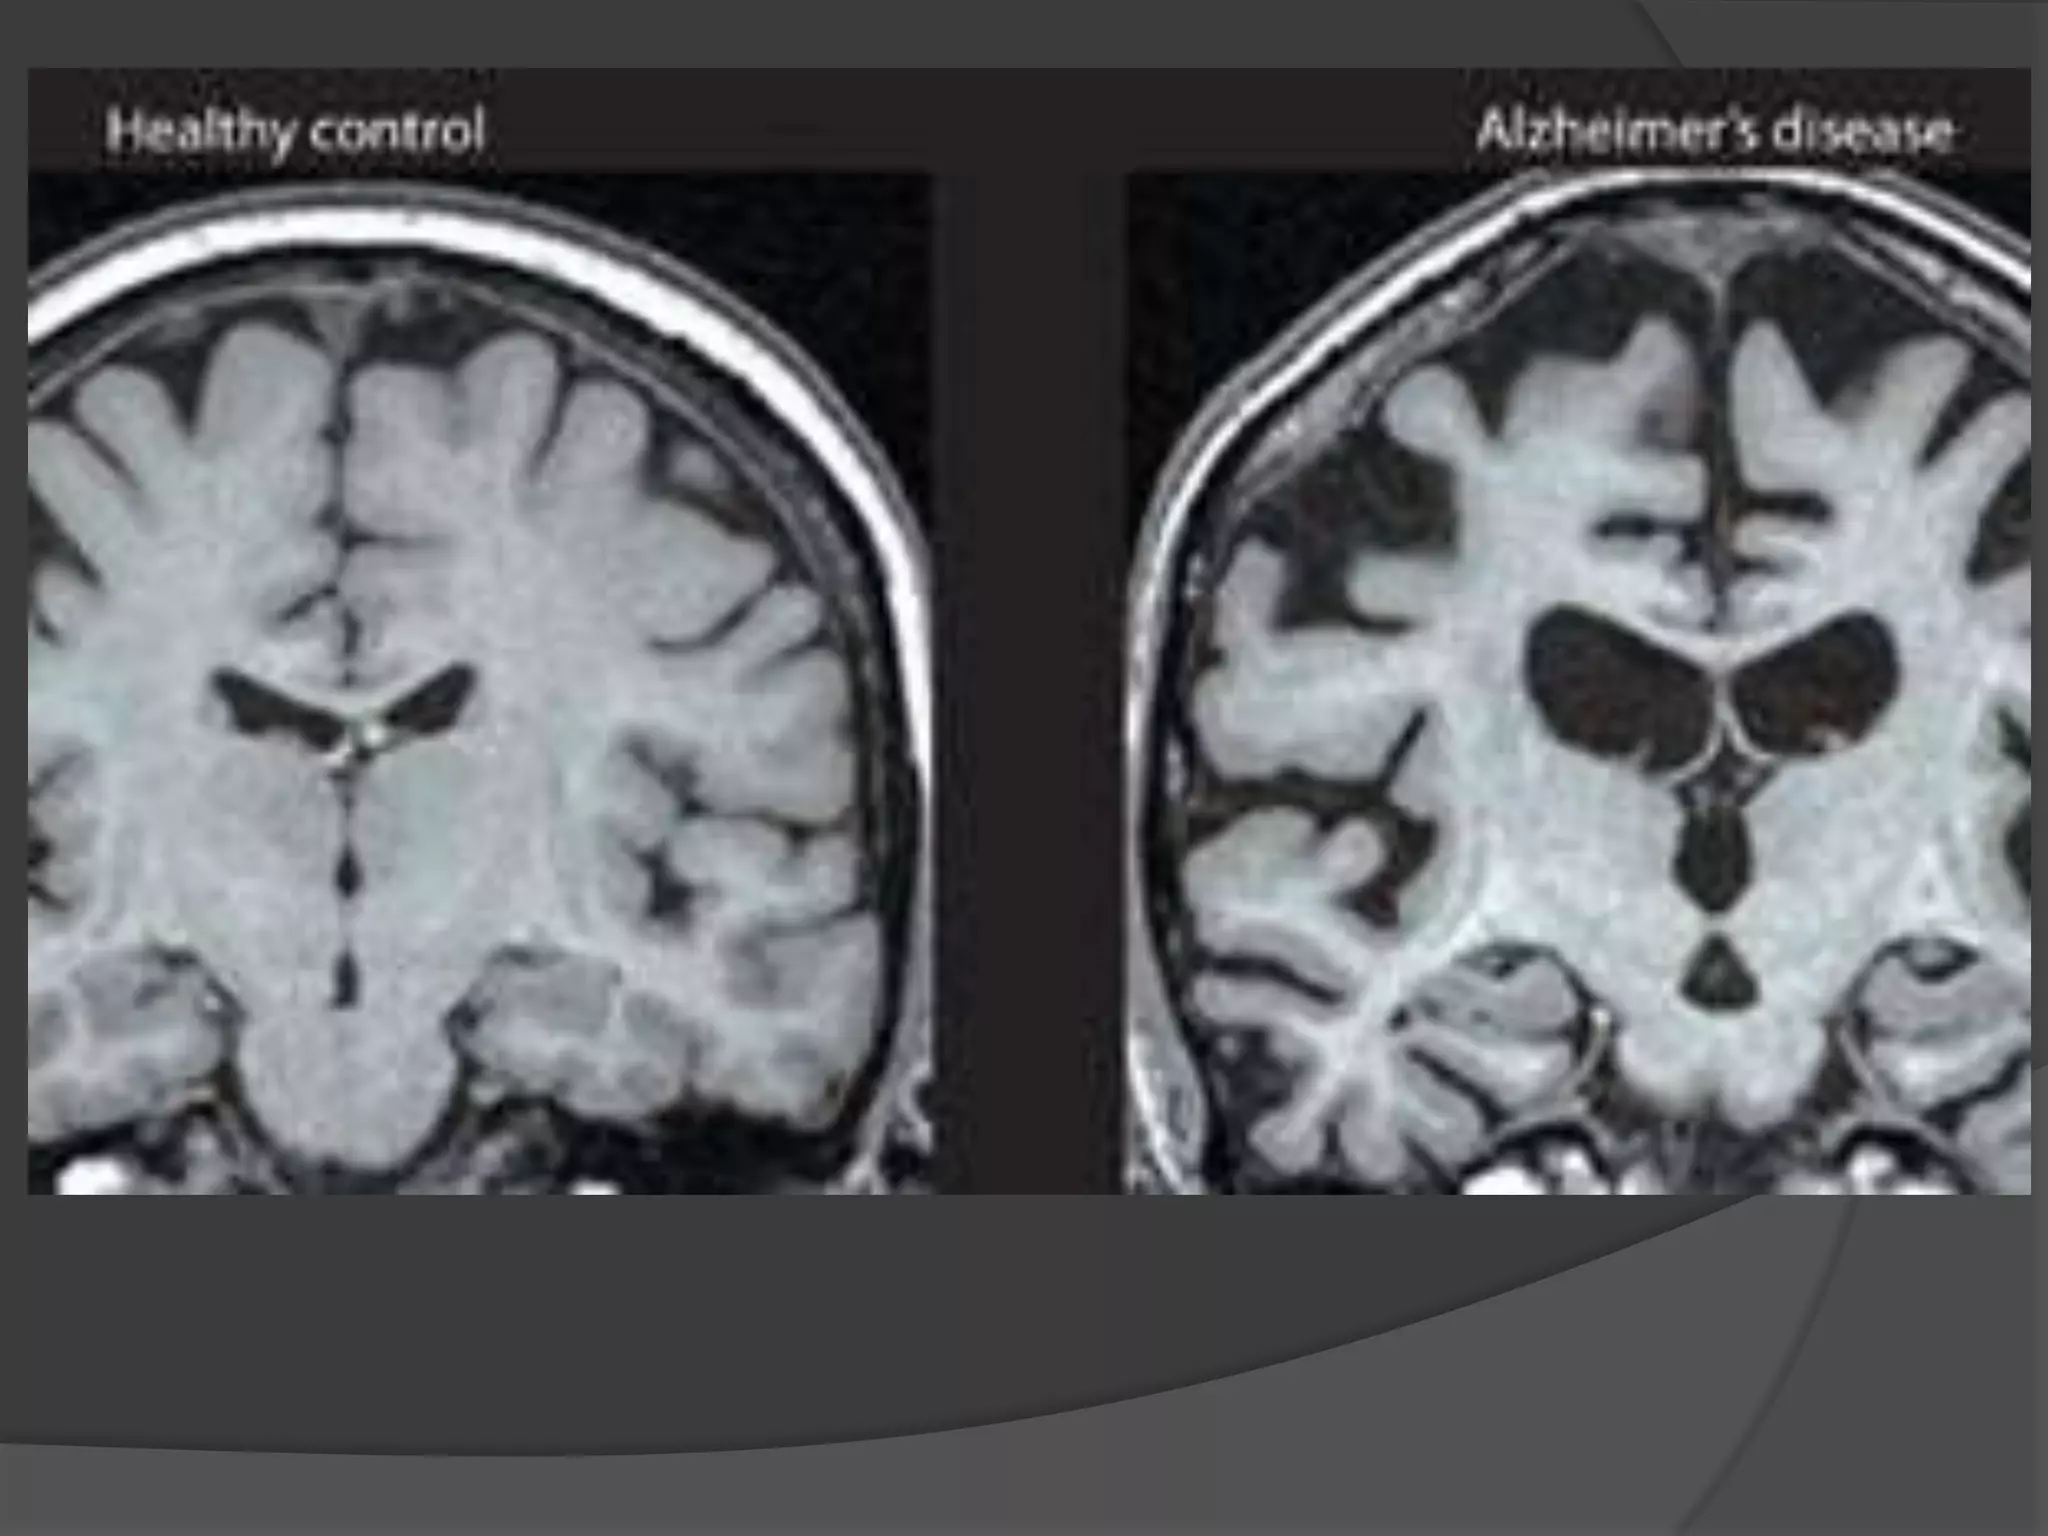

ALZHEIMER’S DEMENTIA

Structural imaging

Cerebral atrophy (typical dilatation of lateral

ventricles & widening of cortical sulci) particularly in posterior temporal & parietal regions &

 specific brain regions like hippocampus and medial

temporal lobe.



Volumetric MRI reveals shrinkage in vulnerable

brain regions, particularly the medial temporal lobe

& Hippocampus.

Measurements of hippocampus is the most sensitive marker of

pathology of AD early in disease